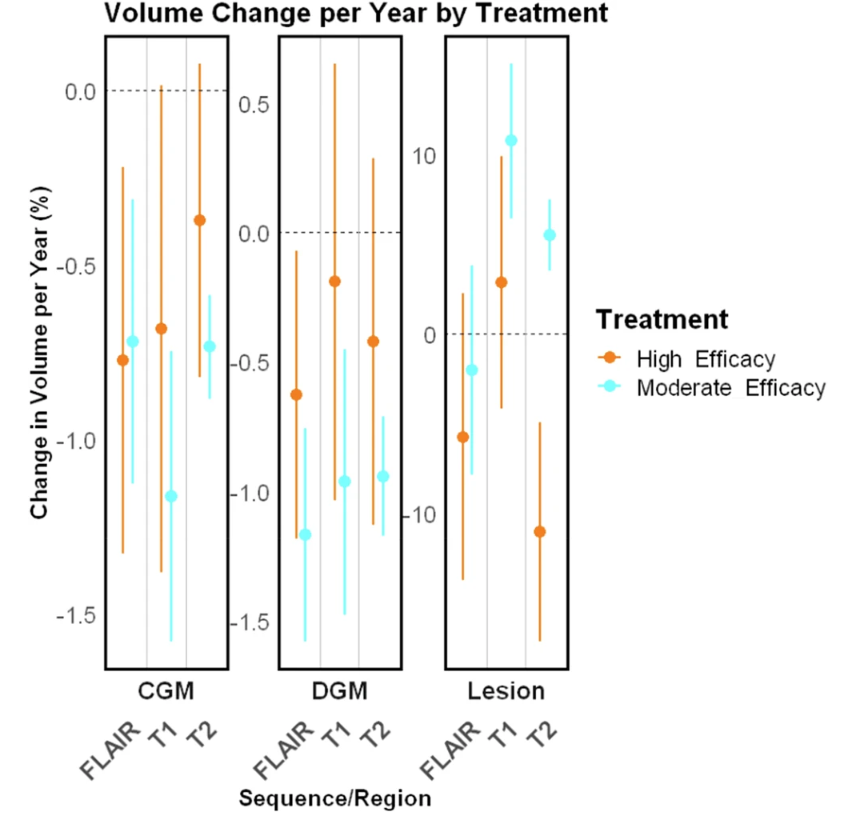

随后,研究人员进行了针对病变治疗效果的纵向验证,涉及多项实验,证明了 MindGlide 在治疗效果检测方面的有效性,如在 SPMS 和 PPMS 试验中,治疗组的病变体积累积量低于安慰剂组;在儿科队列中,MindGlide 成功检测了不同治疗组中病变体积的不同变化,如下图所示。

常规护理儿科数据集中脑区域和病变体积的纵向变化

下图显示了三者对区域脑容量的评估,结果显示,与纵向 SAMSEG 或 WHM-Synthseg 获得的测量结果相比,MindGlide 的测量结果显示治疗组之间的治疗效果更好。

MindGlide、SAMSEG、WHM-Synthseg 纵向脑区变化及病灶体积比较